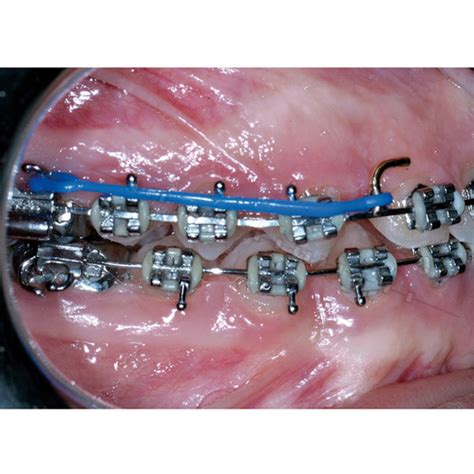

El tie back es una técnica ortodóntica que utiliza ligaduras elásticas o metálicas para asegurar el arco de alambre en los brackets. Esta técnica permite un control preciso del movimiento dental, facilitando la corrección de maloclusiones y el cierre de espacios.

- Aplicación de ligaduras: Se utilizan ligaduras elásticas o metálicas para asegurar el arco de alambre a los brackets, aplicando la fuerza necesaria para el movimiento dental.